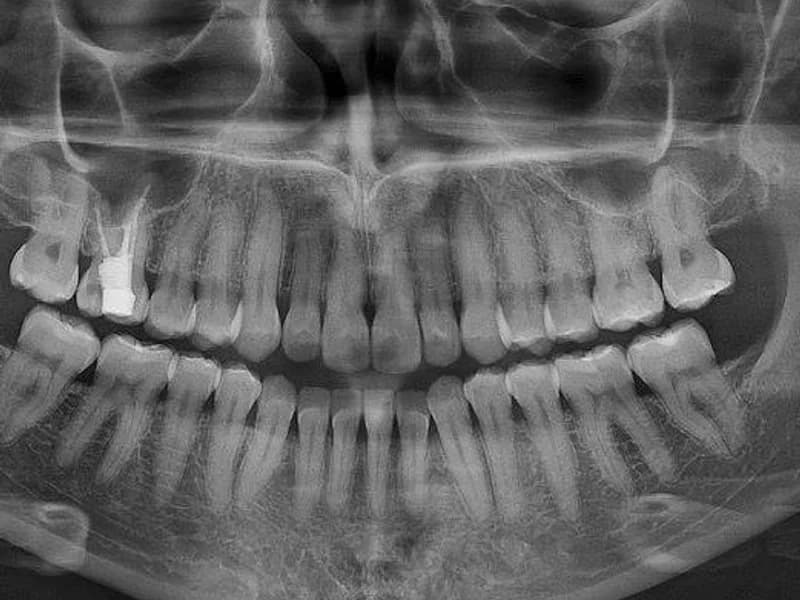

Snimanje digitalnih ortopana, pojedinačnih zuba, sinusa i temporomandibularnog zgloba u Vukovaru.

- –Ortopan

- –Ortopan 1:1

- –Poluortopan

- –Ortopan i intraoralna snimka

- –Segmentna snimka zuba

Ortopan

25 € po jedinici

Ortopan 1:1

Poluortopan

20 € po jedinici

Ortopan i intraoralna snimka

35 € po jedinici

Segmentna snimka zuba